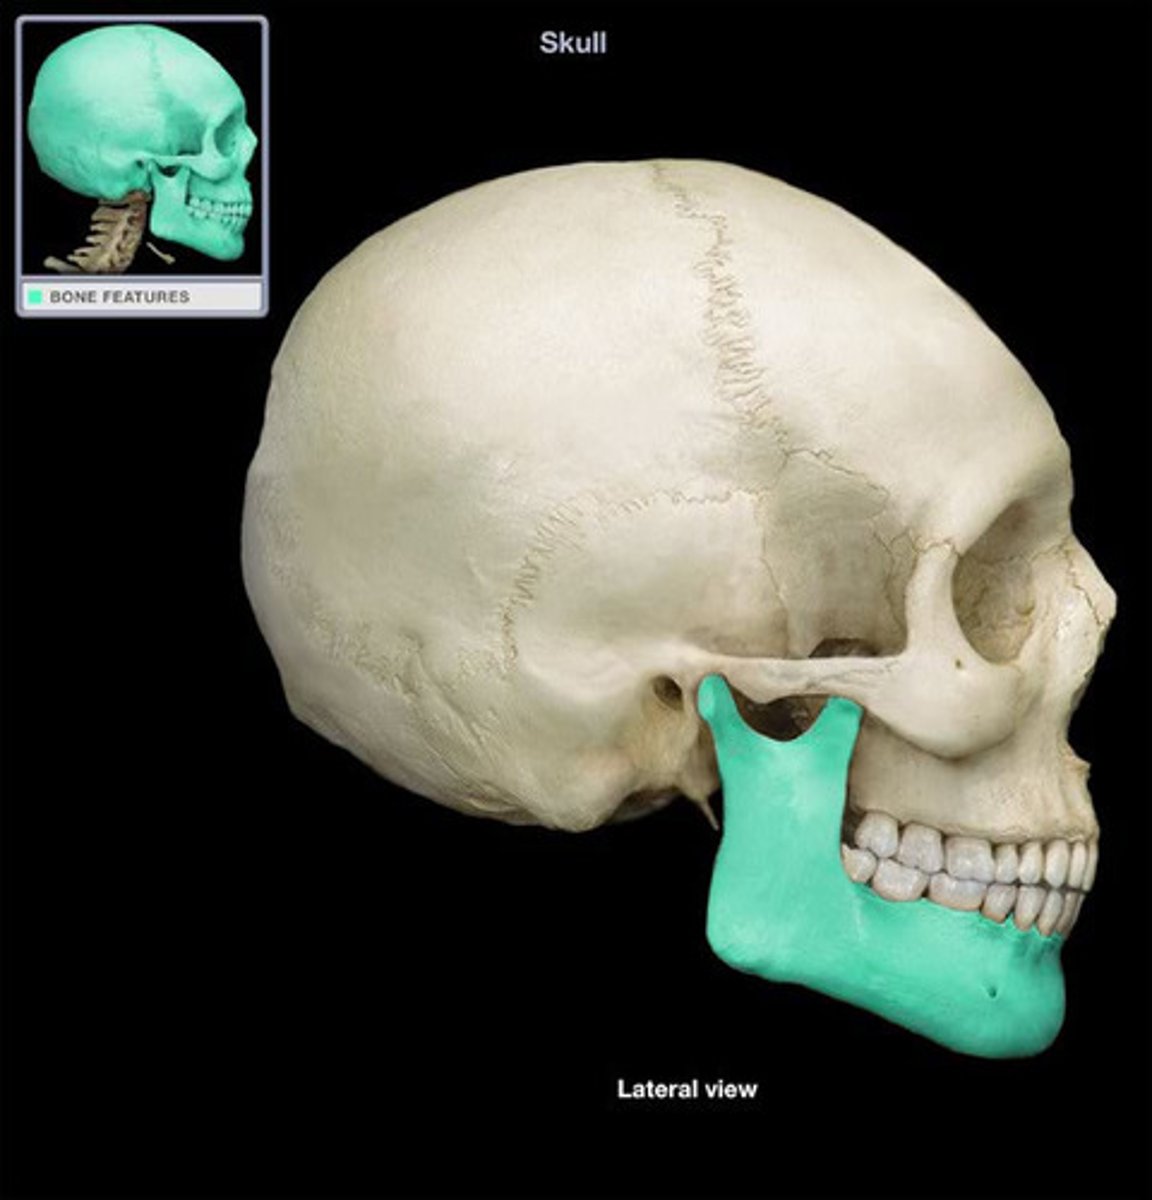

Mandible

Body

Ramus

Angle

Mandibular Condyle

...

Mandibular notch

Coronoid process